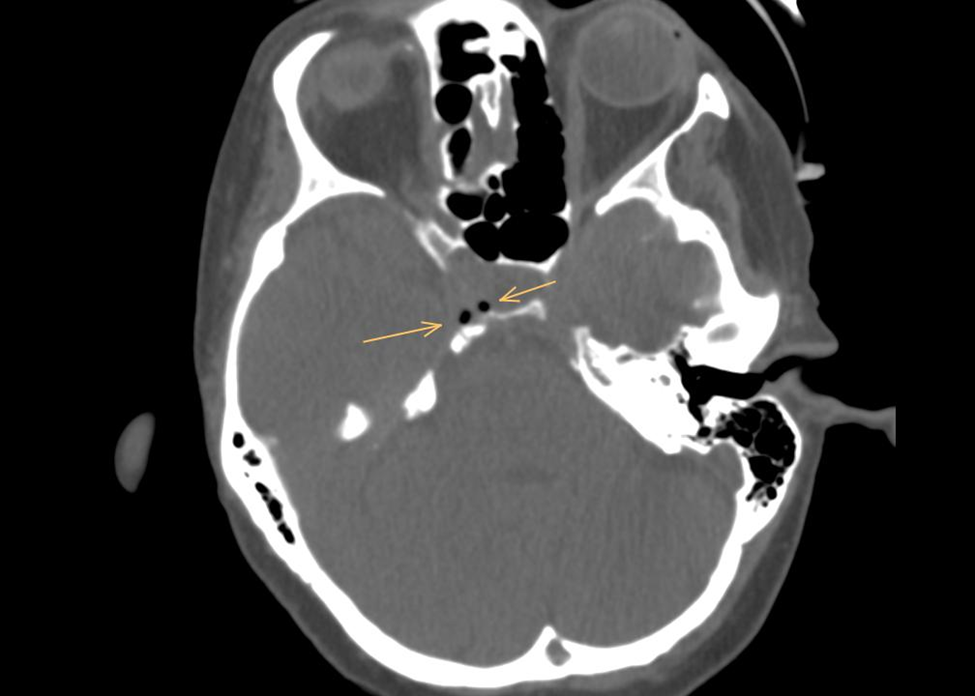

Neurovascular Assessment: An angiographic CT of the skull conducted during the neurological evaluation revealed the presence of air emboli in the cavernous sinus. Notably, echocardiographic assessment ruled out the presence of a patent foramen ovale (PFO), leaving the etiology of the air embolism due to several mechanisms unclear.

Primarily, they include a patent foramen ovale, the presence of right or left intrapulmonary shunts, and the forcing of air through the pulmonary filter. According to the literature on venous embolism, our case suggests that air likely migrated from the arm, passing through the right subclavian vein and entering the internal jugular vein on a cranial path. Once in the internal jugular vein, the air travels through the inferior petrosal sinus, ultimately reaching the cavernous sinus. Patients experiencing gas embolism may not exhibit symptoms; however, they can present with headache, nausea, vomiting, dizziness, or seizures. As the literature indicates, the etiology of these symptoms remains poorly understood.

Figure 3